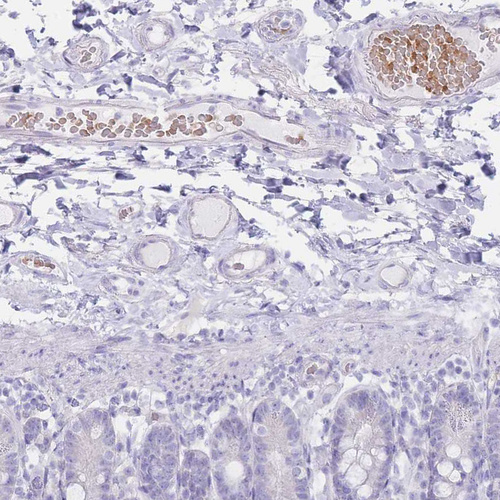

Immunohistochemical staining of human bone marrow shows moderate cytoplasmic positivity in hematopoietic cells.